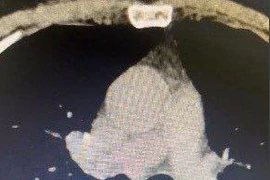

Mới đây, người đàn ông 71 tuổi (TP.HCM) khó thở, mệt mỏi, xây xẩm, choáng váng ho ra 300ml máu đỏ tươi. Sau khi chụp CT cho thấy người đàn ông bị di chứng giãn phế quản tăng sinh mạch máu phế quản sau lao phổi.